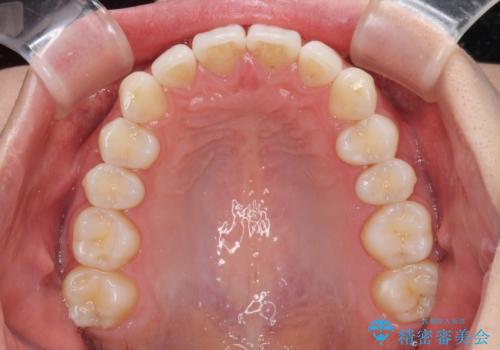

- 上下前歯の叢生を気にして来院された患者様です。

以前矯正をした後戻りということで、歯列不正はそれほど大きくなかったため、インビザライン・ライトを用いて矯正治療を行うこととしました。

インビザラインは1日に22時間を目安に装着していただきますが、装着時間が十分でないとシミュレーション通りに動かないことがあります。

前歯のデコボコが残っており、シミュレーション通りに動いていない部分がありましたが、再矯正であることやご本人の満足いくところまでデコボコが改善されたとのことで、治療を終了することとしました。